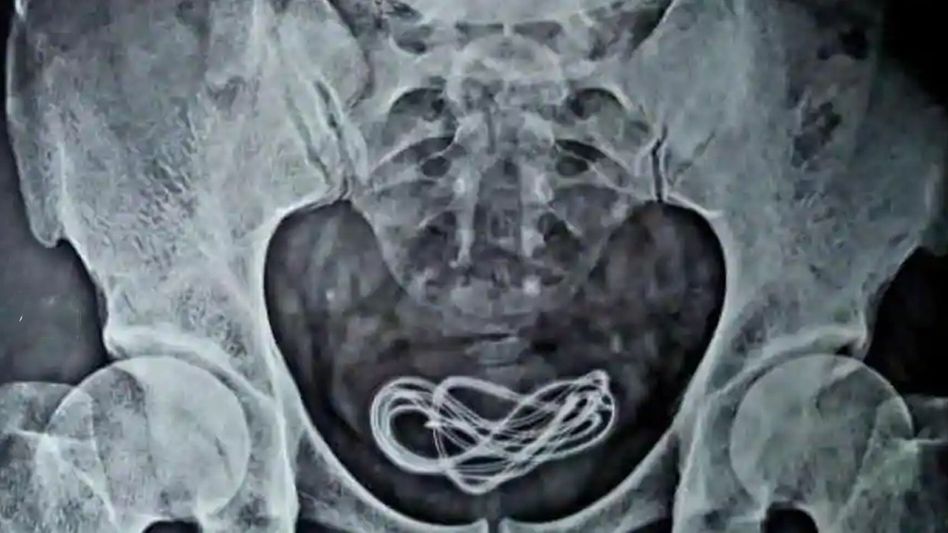

He further added that the matter came to light after conducting an X-ray in the operation theatre. “The X-ray revealed that the cable was in the person’s urinary bladder,” he said while adding that the cable was removed successfully.

“He lied us that he had consumed headphones through the mouth, but in fact, he had inserted the mobile charger cable through his penis. I have been conducting surgeries for 25 years now but this is the first time I got such case,” Islam told Inside NE.